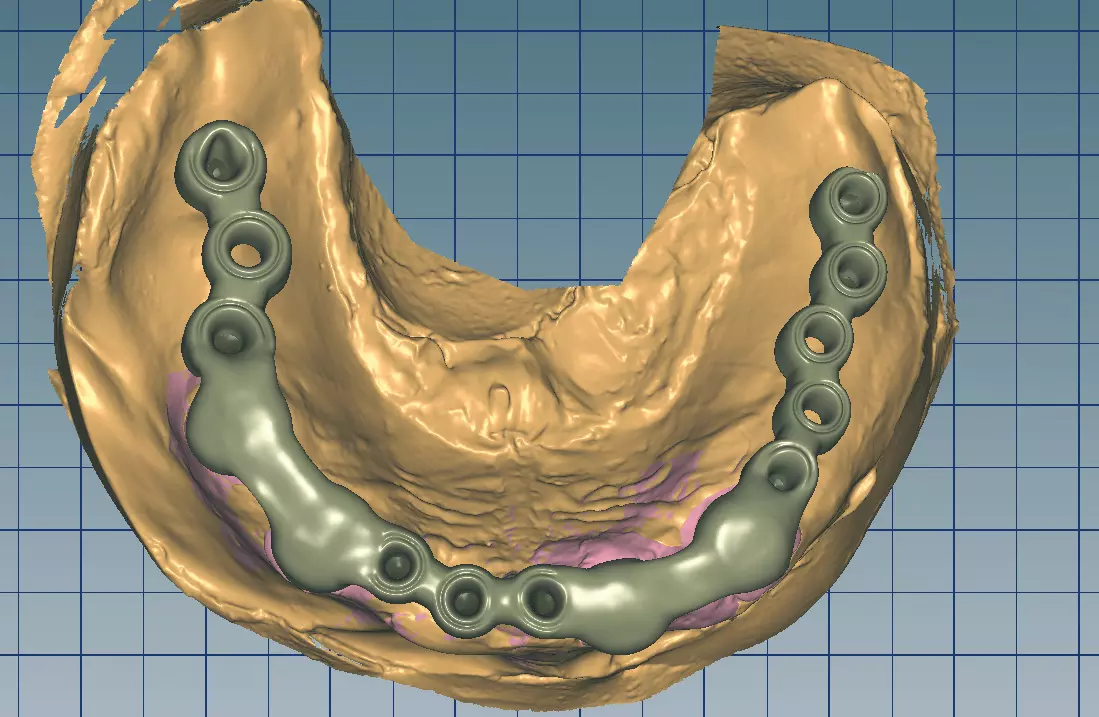

Abb. 35: Digitale Darstellung der Platzverhältnisse zwischen Docklocs, PEEK-Gerüst und Zähnen. Dr. Michael Leistner

Abb. 35: Digitale Darstellung der Platzverhältnisse zwischen Docklocs, PEEK-Gerüst und Zähnen.